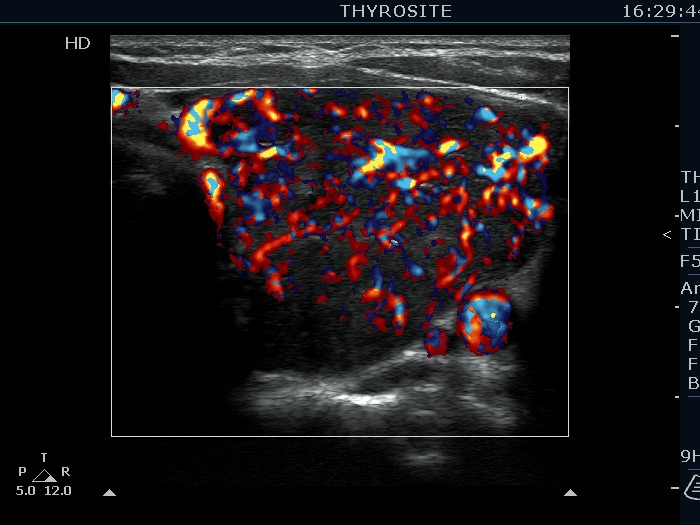

Consecutively operated patients with autoimmune thyroid disease - case 41 (1446) (ultrasonographic picture 8)

Left lobe, transverse scan, color Doppler mode. The vascularization is increased.